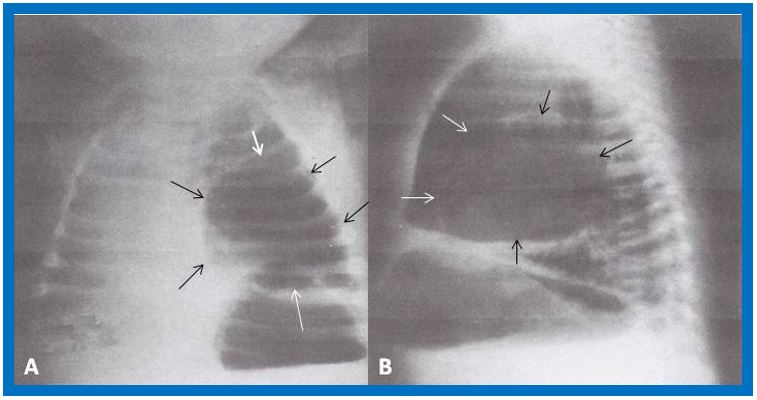

Intermediate strength purified protein derivative (PPD) was positive. Chest roentgenograms were obtained (Figure 5). Based on the history, physical examination, and chest x-ray findings, a diagnosis of endobronchial tuberculosis was entertained. However, prior to beginning treatment, bronchoscopy was performed to appraise the extent of airway encroachment.

nfant with poor appetite, loss of weight, and fever is suggestive of primary tuberculosis. This is particularly so given the patient's exposure to a subject with active pulmonary tuberculosis. The x-rays show hyper aeration of the left lung with a shift of the heart and mediastinum to the right. The left leaf of the diaphragm is also flattened. While there are no areas of infiltration or consolidation were seen, prominent shadows suggesting enlarged lymph nodes were seen (arrows in figure 5). Endobronchial tuberculosis with compression of the bronchus by adenopathy may produce changes seen figure 5.

Even though there was no history of choking or aspiration, the possibility of foreign body aspiration should be considered in this age group. Consequently, bronchoscopy was performed which revealed a peanut in the left main stem bronchus and was extracted during bronchoscopy. The peanut and the adjacent edema of the bronchus caused partial bronchial obstruction and acted as a check valve, so the air entered the left lung but, unable to leave the left lung since the bronchus becomes smaller during expiration, producing the roentgenographic appearance shown in figure 5. The baby improved and the treatment with isoniazid was continued because of the positive PPD.